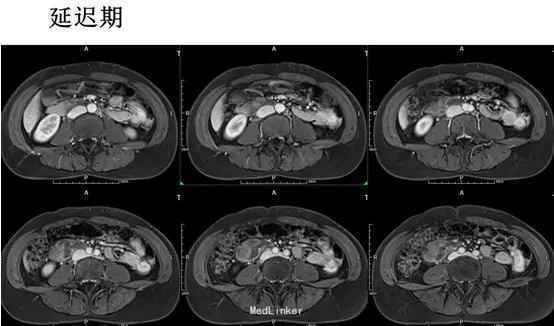

腹部平坦,未见胃肠型及蠕动波,无腹壁静脉曲张,腹软,下腹部轻度压痛,无反跳痛,下腹部扪及一包块,大小约7.5×6cm,质地硬,位置固定,移动性浊音阴性,肠鸣音正常。T 37.5°,P62次/分,R21次/分,Bp140/86mmHg。MR平扫及增强示:中下腹偏右侧见类圆形等长T1长T2异常信号,FS-T2WI呈高信号,DWI(b=800)呈高信号,相应ADC图呈低信号,边界尚清,周围组织受压但未受侵及,注入GD-DTPA后病变强化。

初步诊断:腹膜后肿瘤。行剖腹探查术+腹膜后肿瘤切除术。术后病理:(腹膜后)淋巴管肌瘤病。免疫组化:Vim +、SMA +、HMB-45 少数散在+、Ki-67 5%、MelanA -、ER -、PR -;扁平上皮:CD34 +、CD31部分+、D2-40灶性+。